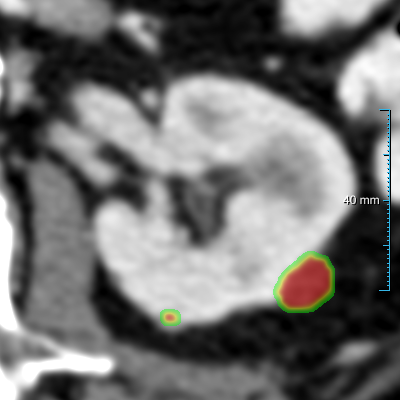

Case 1: 0.346 Dice score

Case 2: 0.266 Dice score

Case 3: 0.777 Dice score

(a) Input slice

Refer to caption

(b) Pred. of experiment 1

(c) Contours

Figure 7: Comparison of three cases on the test set B30 between experiment 1  , the reference standard, and the second observer. (a) shows the original slice. (b) shows the heatmaps (predictions prior to post-processing, using a color table mapping [0,1] from transparent to green to red) of experiment 1  . (c) shows the final predictions (red contours) of experiment 1  , the reference standard (green contours), and the second human observer (yellow contours). The window center and window width used for all slices were 60 HU and 360 HU.

Segmenting kidney abnormalities is challenging due to the similarity between tumors in the collecting system and kidney cysts. For instance, Figure 7 shows three cases from dataset B30 where our method returned some false positives due to the similarity with tumors in the collecting system. Each case shows the kidney abnormality predictions of experiment 1   prior to post-processing in the second row as heatmaps. While the third row shows the post-processed segmentation, reference standard, and second observer as red, green, and yellow contours, respectively. In all three cases, a false positive by our method is present, indicated by an isolated red contour. In case 1, the false positives are abnormalities in the collecting system, which have a similar image intensity as the cysts, similarly, the second observer also segmented one of these abnormalities in the middle region. In case 2, the false positive appears as a small cyst-like region, while in case 3, it resembles an irregular region in the kidney. Figure 9 shows a comparison of the final prediction in annotation format 1 of experiment 1  , the reference standard, and the second observer represented as red, green, and yellow contours, respectively. This figure shows the best and median cases of datasets B20 and B30 and the Dice score of each case computed between experiment 1   and the reference standard.